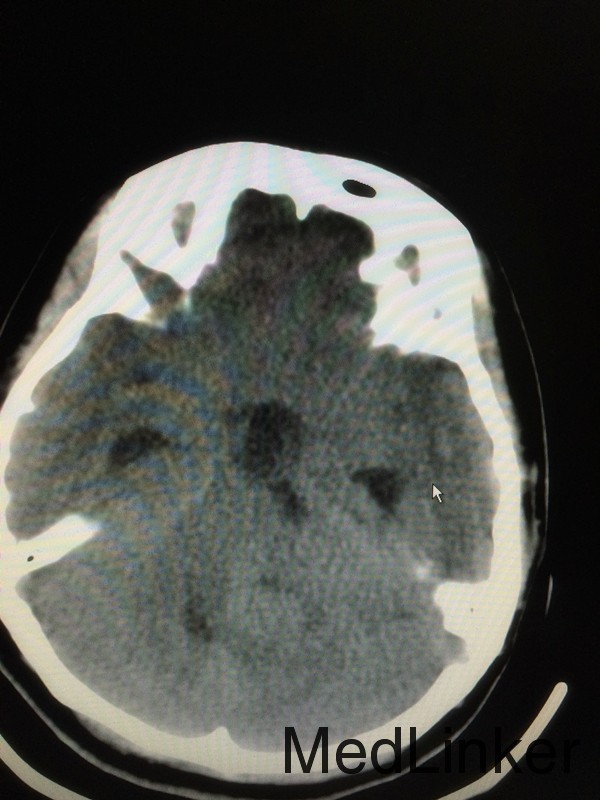

主诉:头晕头痛5月余,伴听力下降视物模糊3个月 病史:患者28岁女性,于5个月前无明显诱因出现头痛头晕,3个月前出现视物模糊,伴耳鸣,于外院行头颅MRI提示:左侧桥小脑角区占位,考虑听神经瘤。

查体:左侧轻微面瘫,左侧面部感觉稍减退,余无特殊 辅助检查:头颅CT提示左侧桥小脑角区类圆形肿物,考虑听神经瘤可能,四脑室受压变窄并右移

诊断:左侧听神经瘤 治疗:行左侧桥小脑角区占位切除术,术后病理提示左侧桥小脑角神经鞘瘤